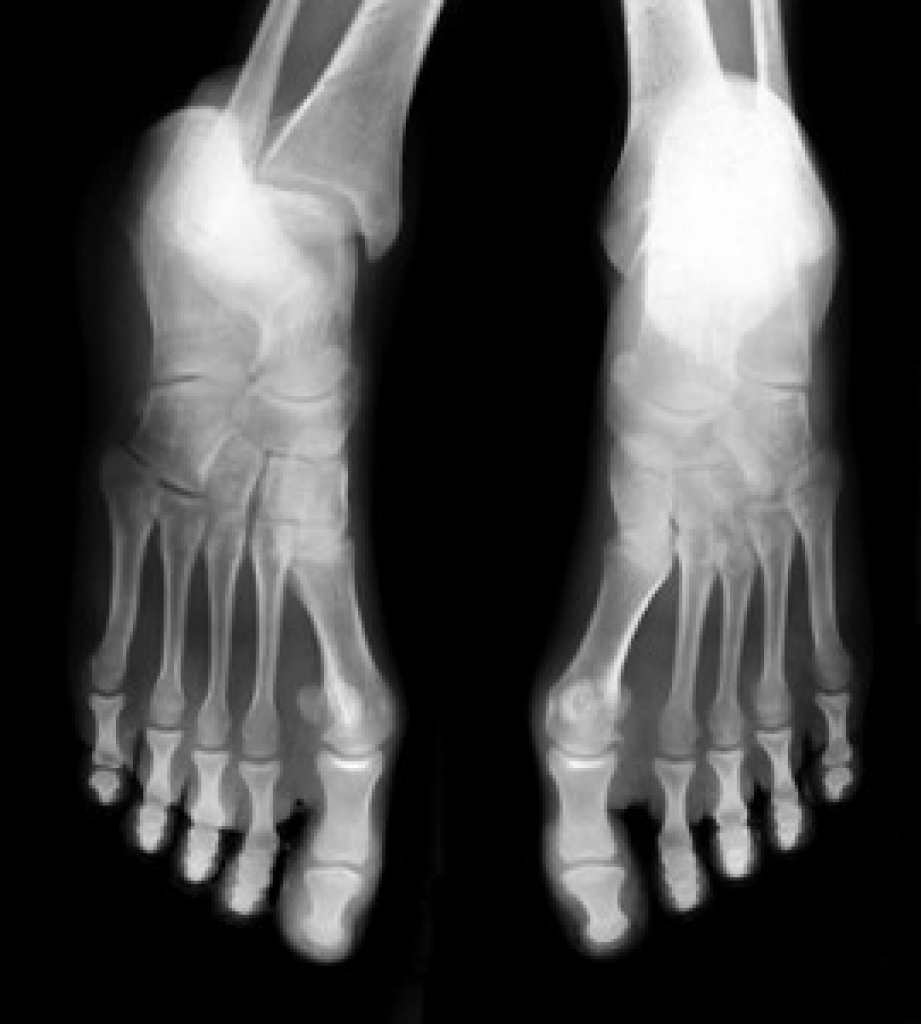

Gout is a type of arthritis caused by a buildup of uric acid in the bloodstream. It often develops in the foot, especially the big toe area, although it can manifest in other parts of the body as well. Gout can make walking and standing very painful and is especially common in diabetics and the obese.

Gout can easily be identified by redness and inflammation of the big toe and the surrounding areas of the foot. Other symptoms include extreme fatigue, joint pain, and running high fevers. Sometimes corticosteroid drugs can be prescribed to treat gout, but the best way to combat this disease is to get more exercise and eat a better diet.